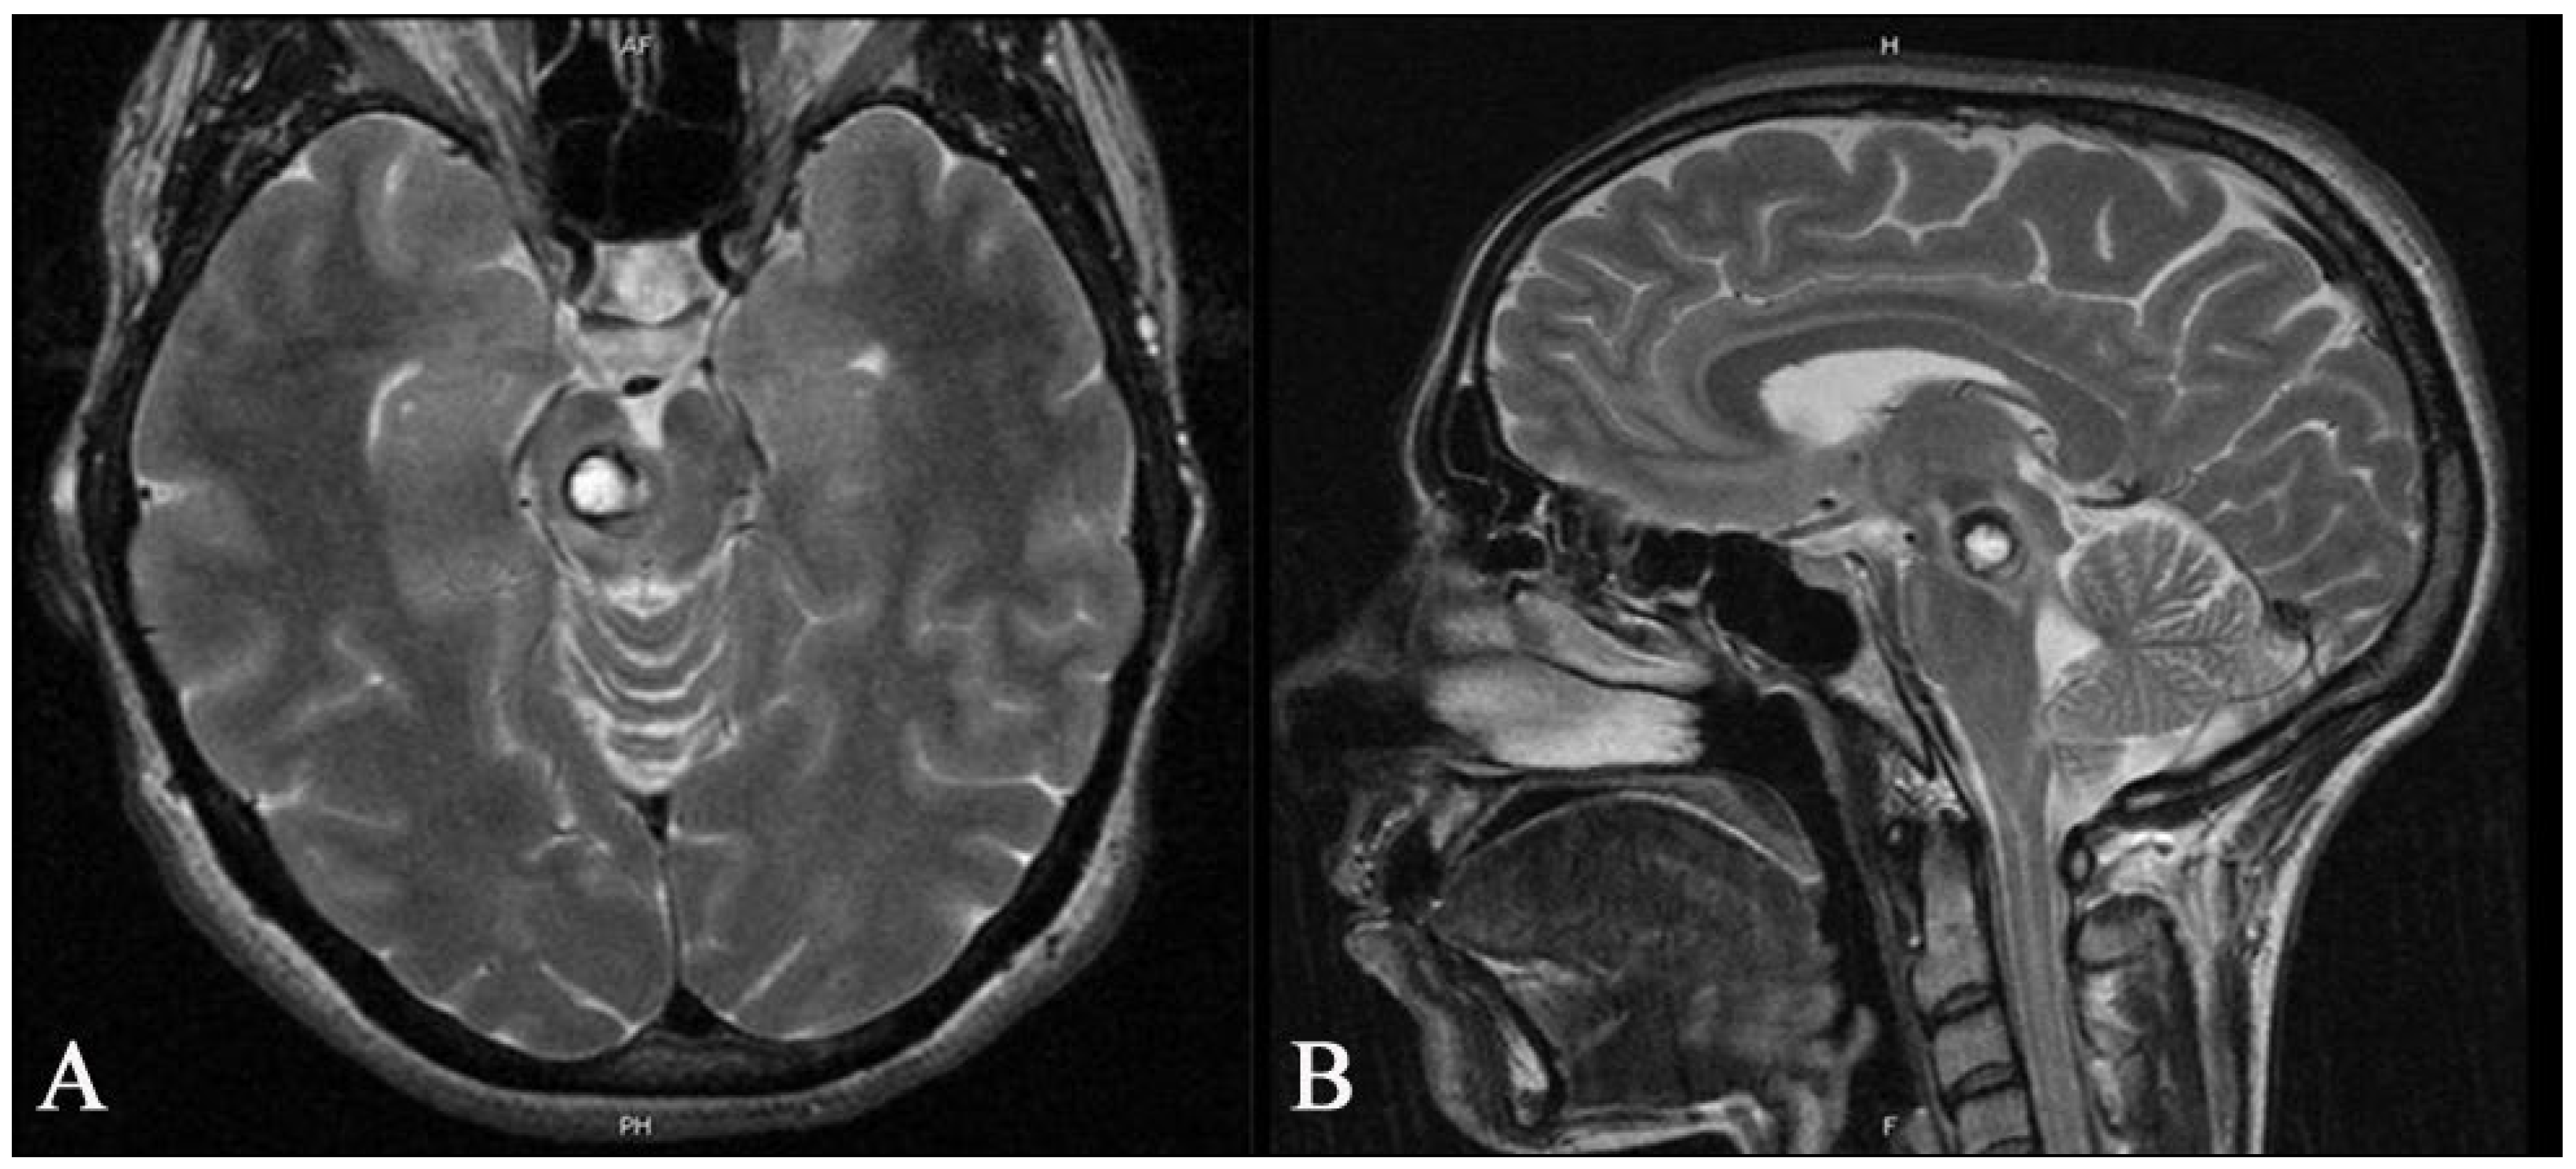

Figure 5. Preoperative axial (A) and sagittal (B) T2 MR images of a 35-year-old woman showing a deep-seated cavernous malformation in the midbrain on the right side. The patient had been suffering from headaches and gait disturbances for several weeks.